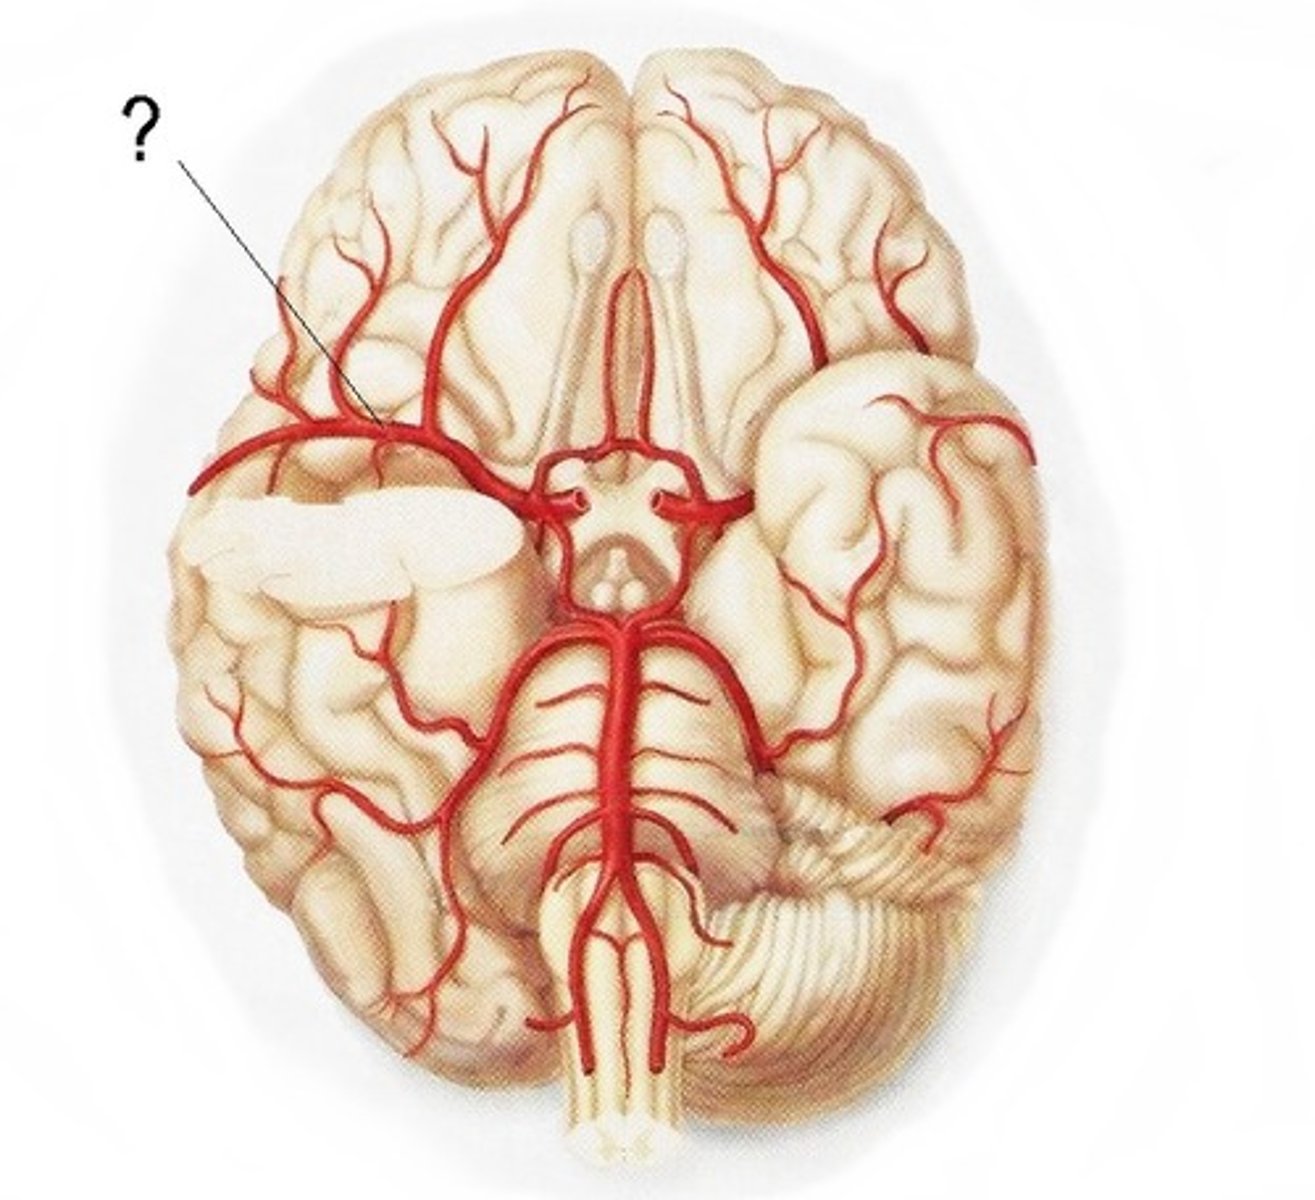

vertebral arteries

Arteries that ascend the vertebrae, enter the base of the skull, and join together to form the basilar artery. Travel through foramen magnum to reach the pons.

internal carotid arteries

this artery branches off the common carotid arteries, travel up into the skull through the carotid canal, and then divide to form the anterior and middle cerebral arteries.

anterior cerebral arteries

two large arteries, arising from the internal carotid arteries. Travels anteromedially to the median longitudinal fissure where it supplies the superior and medial aspects of the frontal and parietal lobes.

middle cerebral arteries

two large arteries, arising from the internal carotid arteries. Dives into the lateral fissure to travel to the lateral aspect of the brain, where it supplies the majority of the temporal lobe and a large portion of the frontal and parietal lobes.

posterior cerebral arteries

Two large arteries, arising from the basilar artery, that supply the posterior aspect of the brain, including the occipital lobes, as well as the inferior portion of the temporal lobes.

anterior communicating artery

Connects the two anterior cerebral arteries before they enter the median longitudinal fissure

posterior communicating artery

small arteries that connect the posterior cerebral and internal carotid arteries.

basilar artery

arises from the vertebral arteries and runs along the pons before dividing into posterior cerebral arteries.